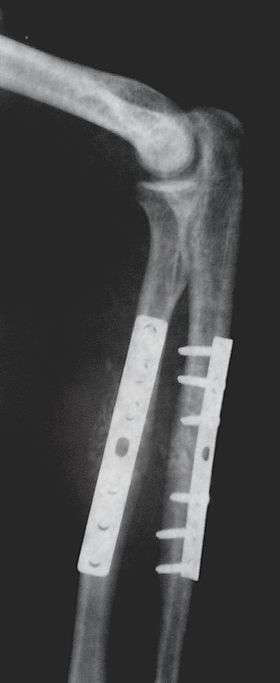

Orthopaedic implants help alleviate issues with the bones and joints of the body. They're used to treat bone fractures, osteoarthritis, scoliosis, spinal stenosis, and chronic pain. Examples include a wide variety of pins, rods, screws, and plates used to anchor fractured bones while they heal.[1][2][3]